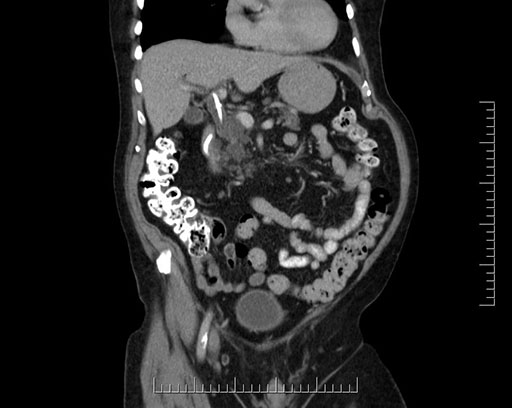

Coronal - stented